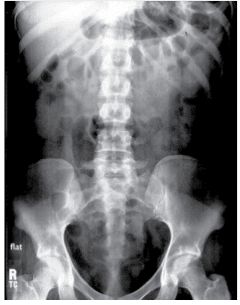

UIV com Rim em Ferradura

Fase nefrográfica de uma UIV demonstrando a fusão dos polos inferiores dos rins, caracterizando o rim em ferradura.